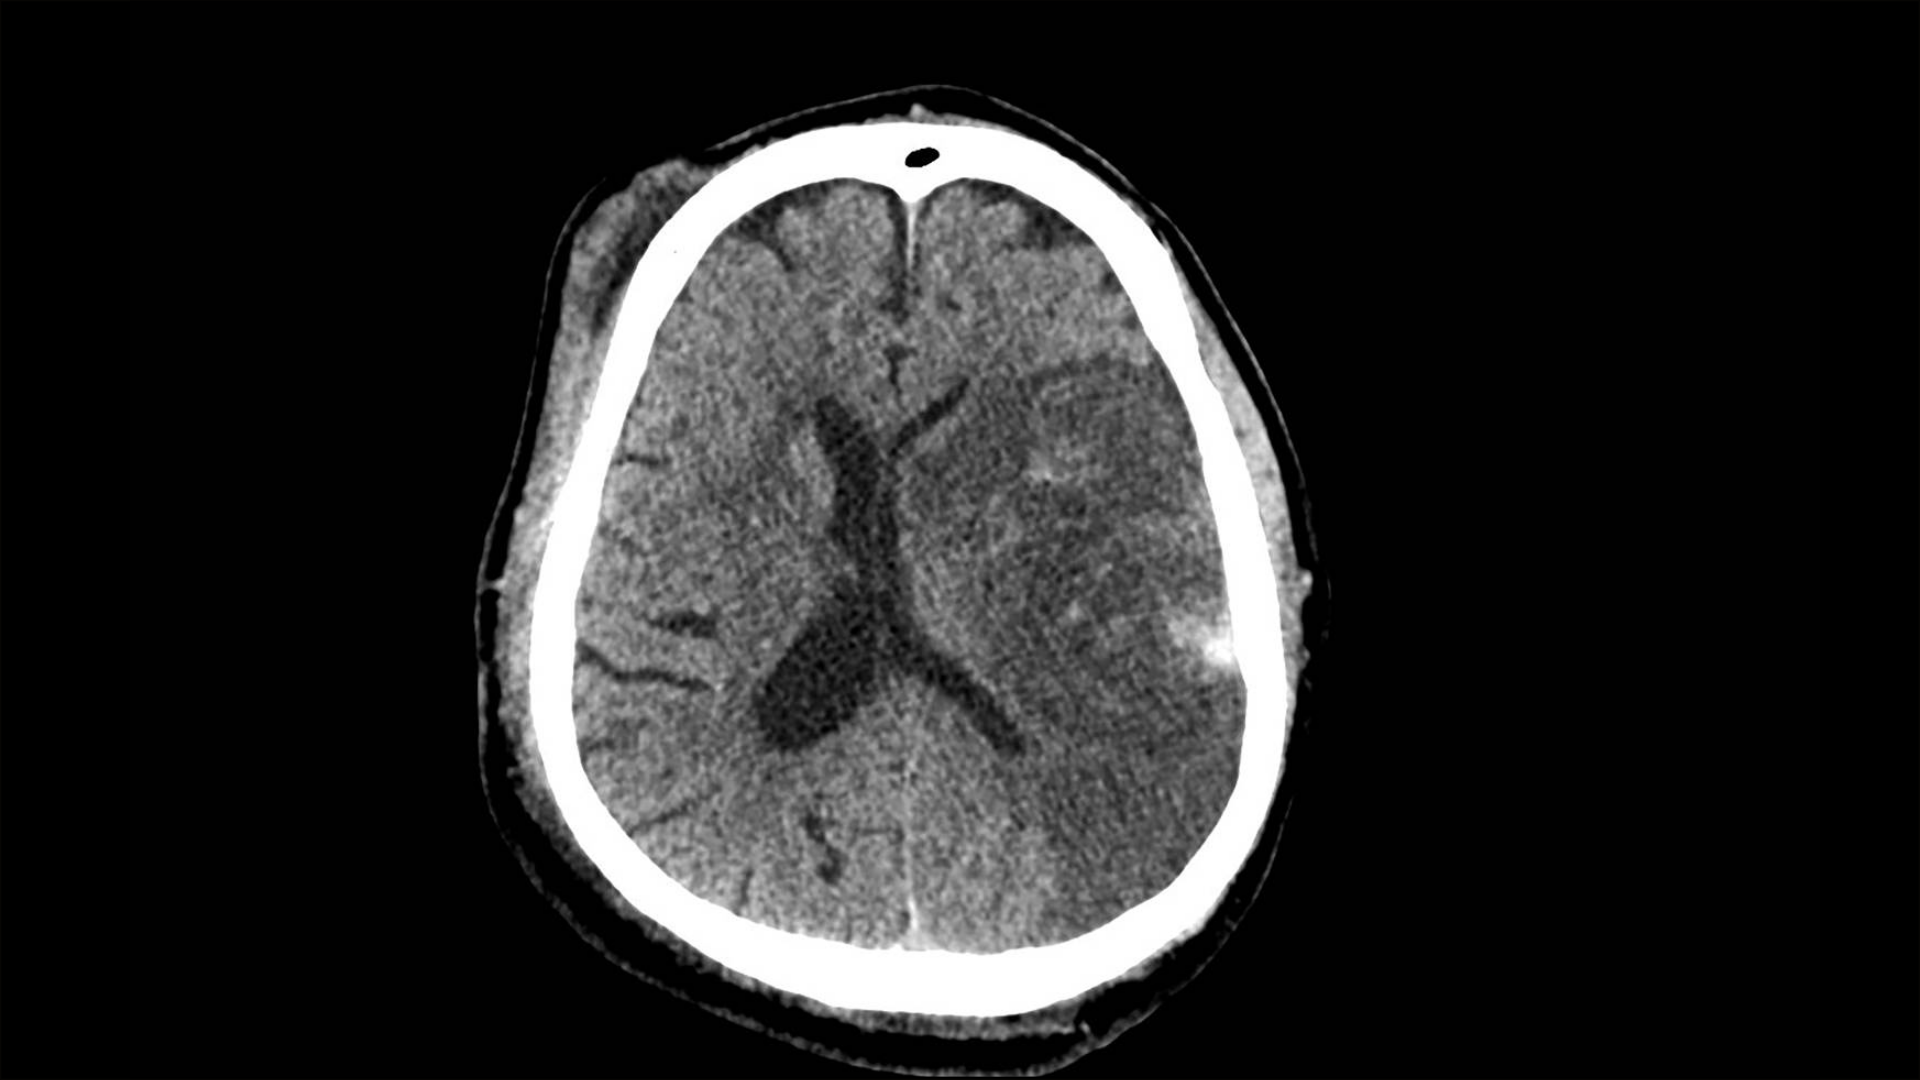

- Imaging: CT before randomisation was not mandatory; if CT was available and showed intracranial haemorrhage, the patient was not eligible for randomisation to aspirin/heparin for presumed ischaemic stroke.

- CT timing (a key co-variable influencing misclassification of haemorrhage): CT done before randomisation in 67%, after randomisation in 29%, and never in 4%.

- CT imaging not mandatory prior to randomisation (CT before randomisation 67%; after 29%; never 4%), increasing diagnostic heterogeneity and risk of haemorrhage misclassification at baseline.